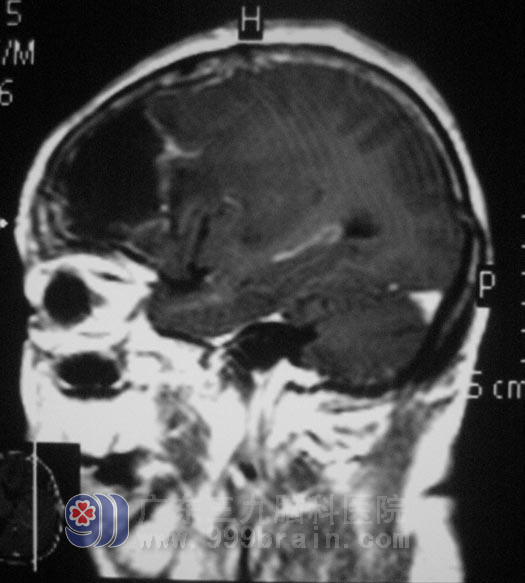

上面就是从马婆婆颅内切出的、折磨着她不能说话、不能走路、直径约6cm的肿瘤。http://www.999brain.com/

几经周折,他们来到广东三九脑科医院。入院时,马婆婆精神差,呈嗜睡状,右下肢I级,右上肢II-III级。综合神经外科 鲁明主任根据影像检查,考虑肿瘤有卒中的可能。9月5日,由鲁明主任主刀,在全麻下经改良翼点入路行左额部占位性病变切除术,术中见额部颅骨明显被肿瘤侵袭,脑组织张力较高,在显微镜下从病变周围沿硬膜逐步分离,整块切除病变组织,肿瘤大小6.3cm×5.0cm×5.4cm,手术过程顺利,术中出血约400ml。

术后第一天,马婆婆的语言功能、肢体活动功能基本恢复。拆完线后便能自行下床活动。儿女们都没有想到母亲手术后会出现这么满意的结果。术后病理结果为:(左额部)脑膜瘤,WHO I级。http://www.999brain.com/